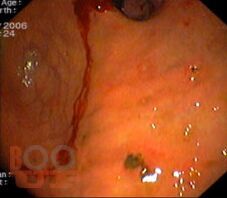

Вторая части учебного пособия «Осложнения язвенной болезни желудка и двенадцатиперстной кишки» посвящена язвенным желудочно- кишечным кровотечениям. В настоящем пособии освещены вопросы этиологии и патогенеза острых желудочно-кишечных кровотечений, их классификация, клиническая картина, современные методы диагностики. Подробно изложены принципы консервативного, эндоскопического и хирургического лечения данной патологии.